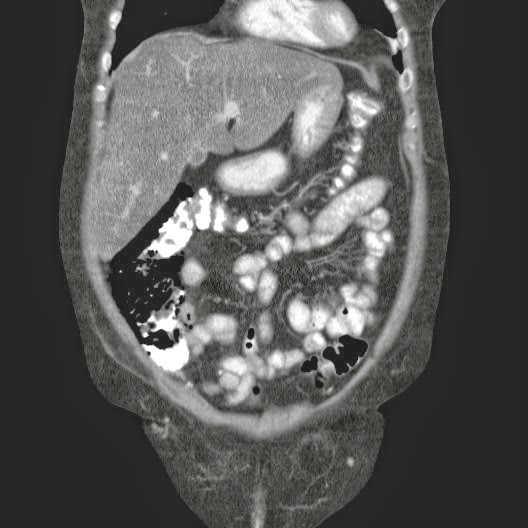

Caso Interesante #4

Adulto masculino, 1 semana de fiebre y malestar general.

¿Dónde esta ubicado el hallazgo?